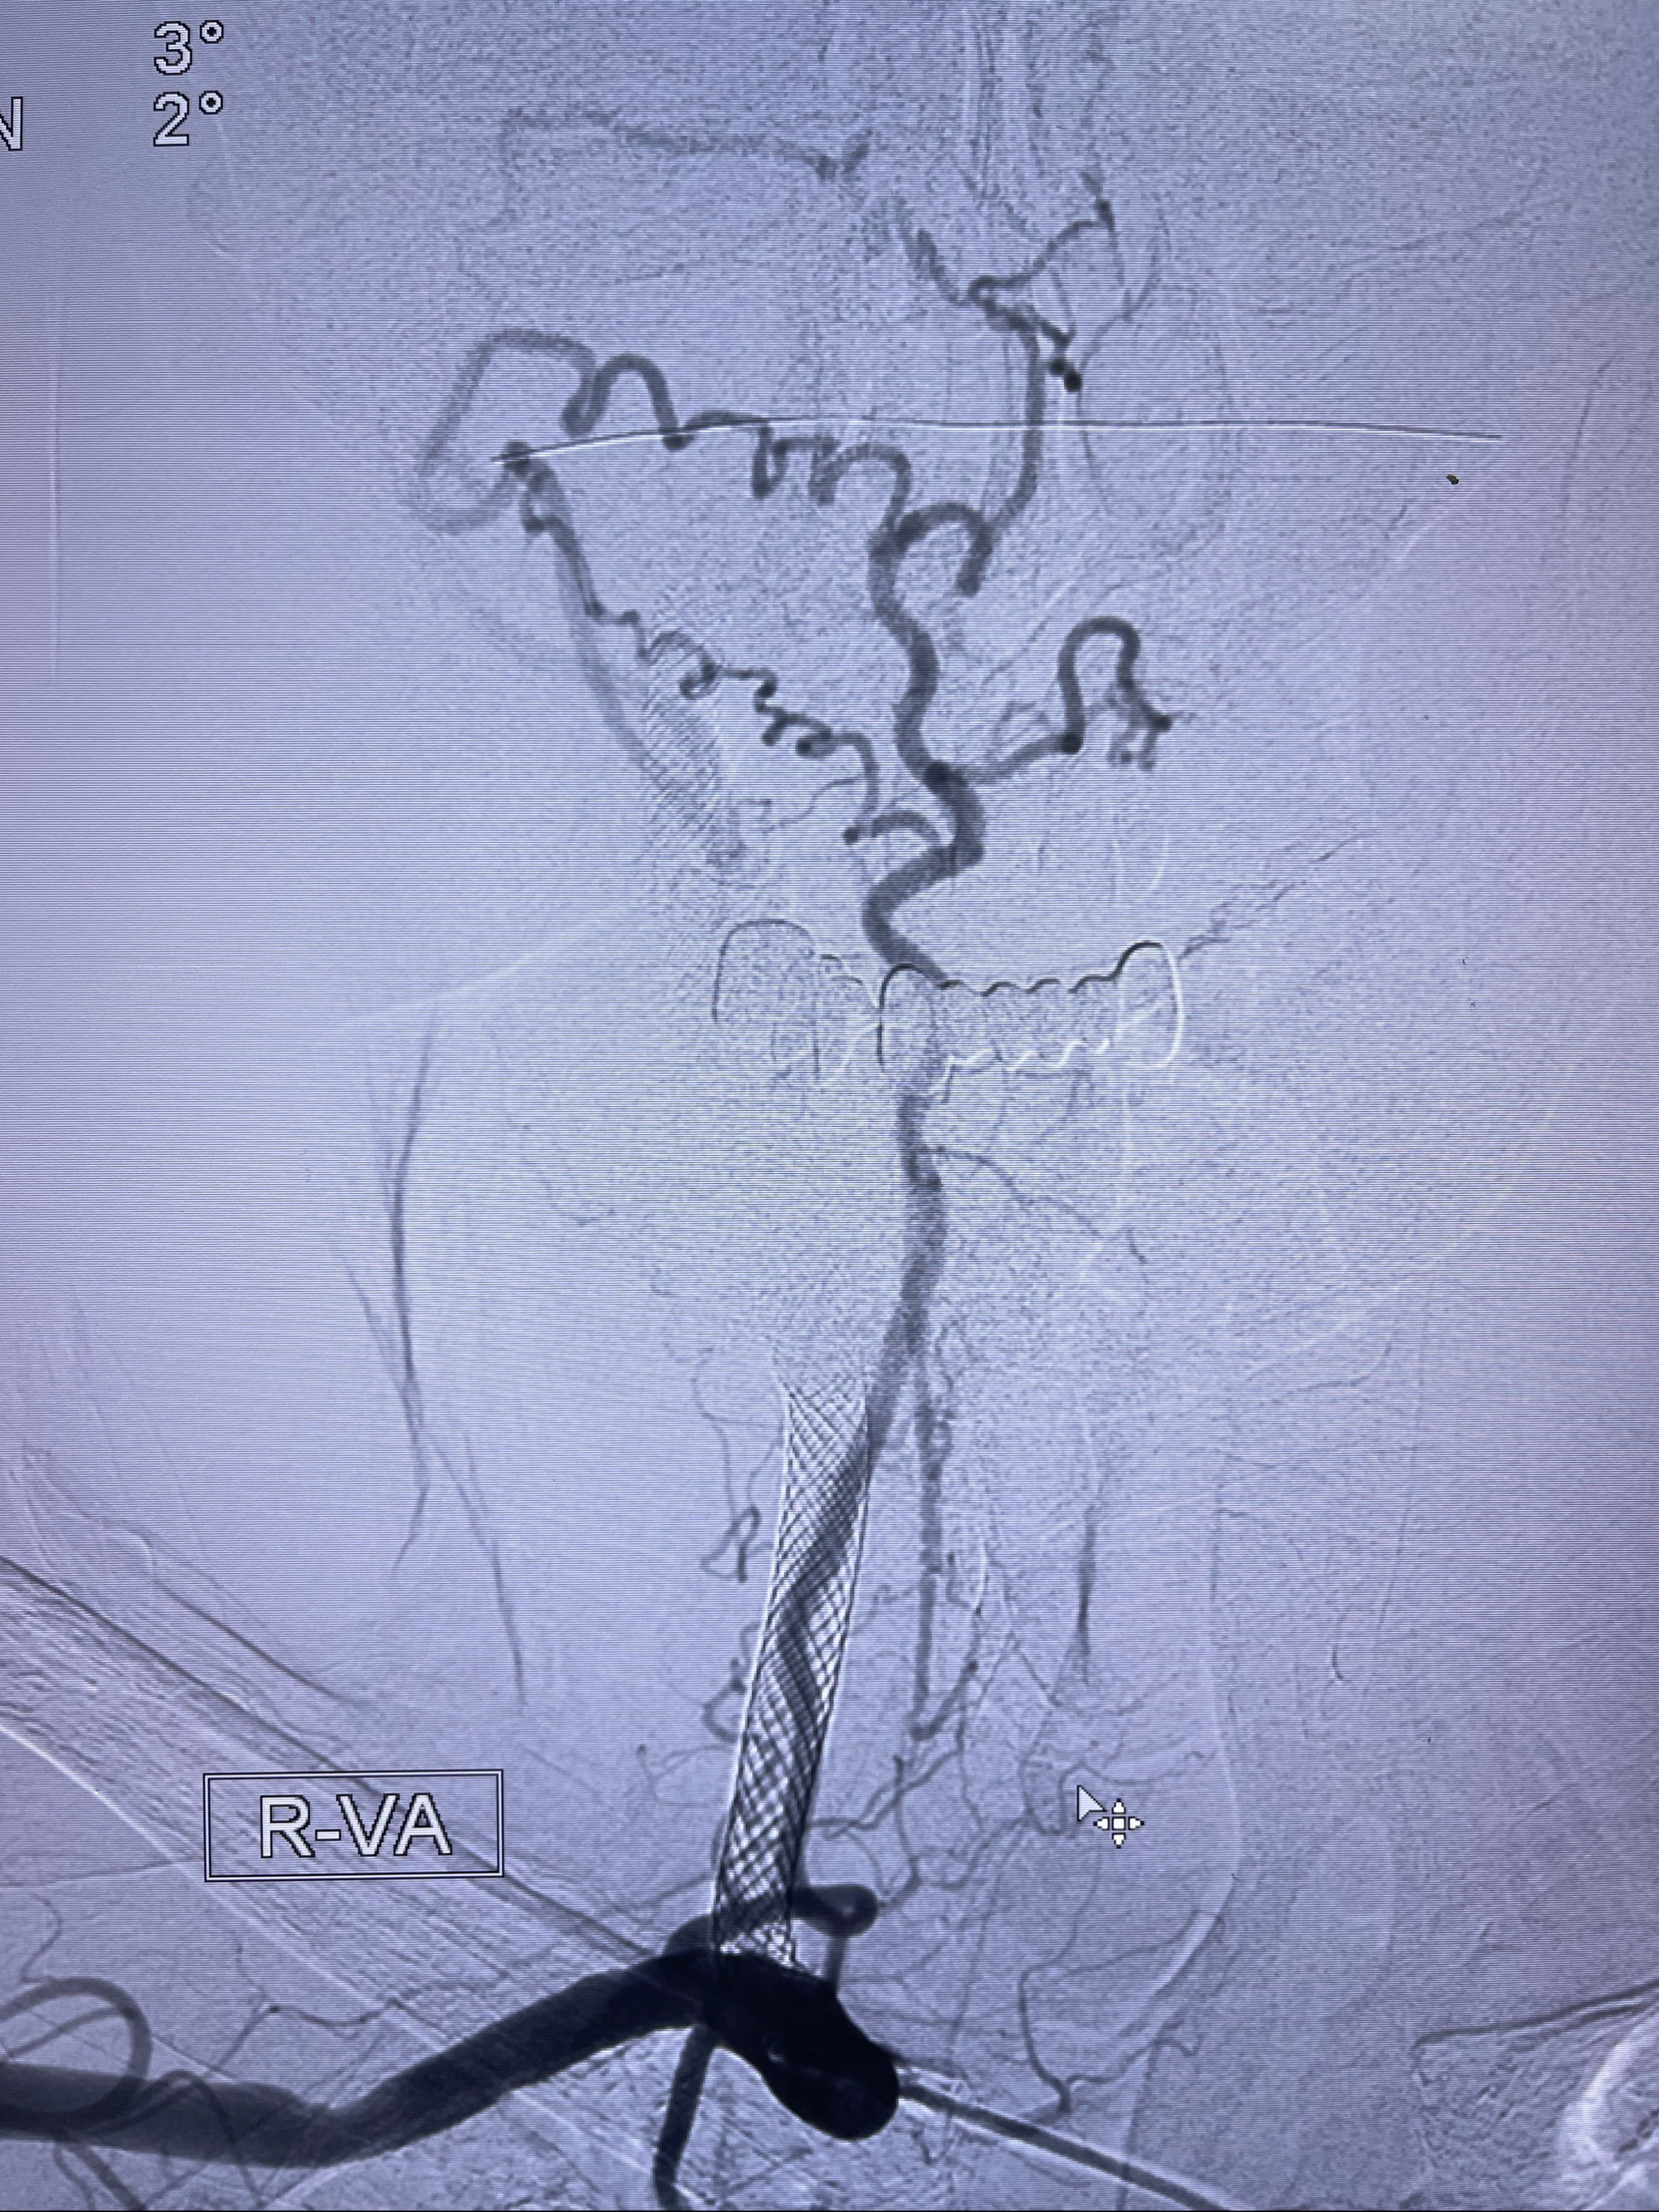

2023-07-10DSA:右侧颈内动脉岩骨段夹层伴中偏重度狭窄改变,左侧颈总动脉闭塞、右侧颈外动脉由右侧肋颈干甲颈干吻合代偿

箭头所示为颈内动脉岩骨段重度狭窄,结合MRI,考虑为肿瘤侵犯右侧颈内动脉

箭头以近至支架段管腔不规则狭窄

右侧椎动脉可见吻合代偿右侧颈外动脉

双抗准备后于2023-07-13在全麻下行右侧颈内动脉功能保护

088NeuroMAX100cm长鞘在125cmMPA及黑泥鳅导丝引导下超选择性插入右侧颈内动脉支架内

经导引导管造影显示支架远端颈内动脉不规则狭窄伴局部充盈缺损,同时行全身肝素化5ml

路径图下4-20mm球囊在导丝引导下超选择性至狭窄段,以6-8个大气压扩张,持续30s

泄除球囊造影显示局部管腔扩张佳

后移球囊至颈段狭窄段,以8-12个大气压扩张,持续30s后泄除球囊

即刻造影显示狭窄扩张佳